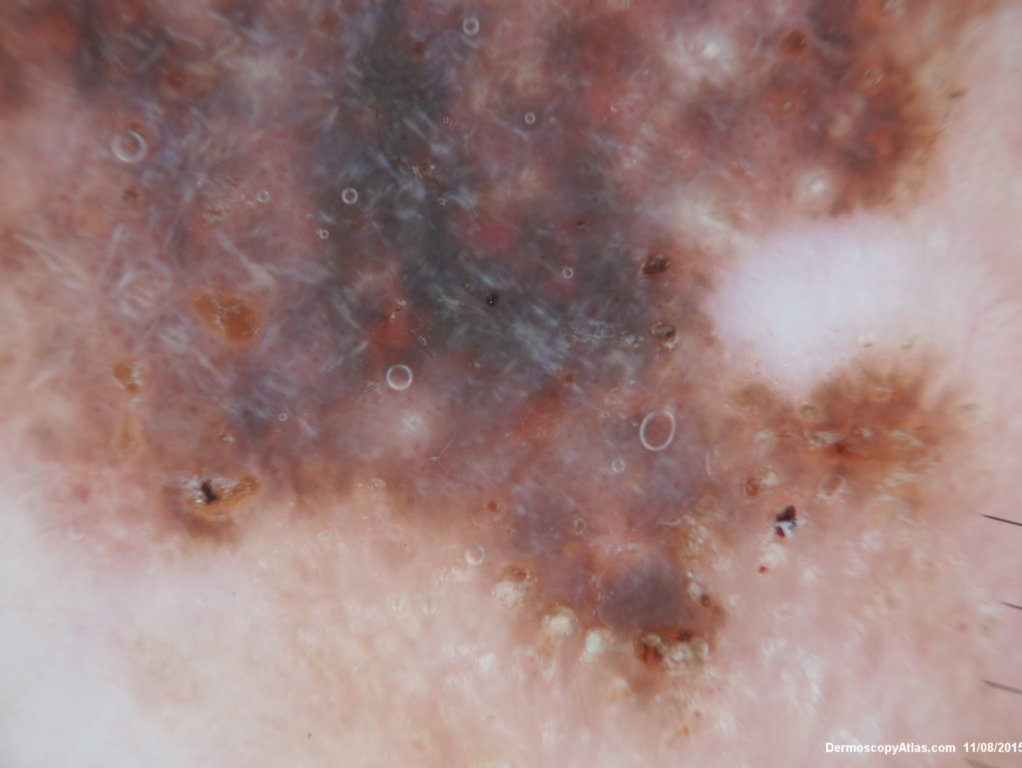

Site: Back

Diagnosis: Seborrhoeic keratosis irritated

Sex: M

Age: 92

Description: Pigmented lesion back

This lesion looked darker than the many other seborrhoeic keratoses on this elderly man's back. It was thought there might be a lentiginous proliferation of atypical melanocytes in the lesion . Also the multiple colours and the white lines were unusual for a seborrhoeic keratosis. However pathology of a large shave biopsy excision showed only a pigmented thick seborrhoeic keratosis with increased pigment in normal basal keratinocytes. The blue colour was because of the depth of the lesion ie thick. No idea why the white lines!